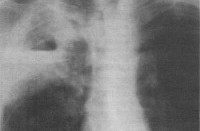

J18.2 Гипостатическая пневмония неуточненная